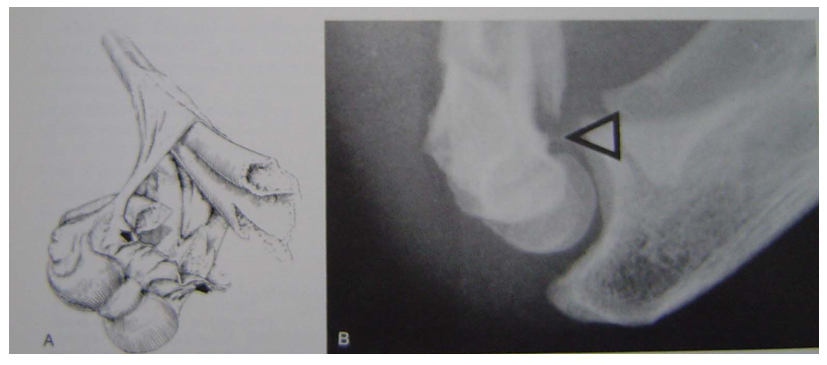

Baumann角

A 肱骨干中线a

B 作a的垂线b

C 通过外髁骺线

∠A,原始Baumann角

∠B ,现在Baumann角

正常72度[64~81],81度以内,不会发生肘关节内翻